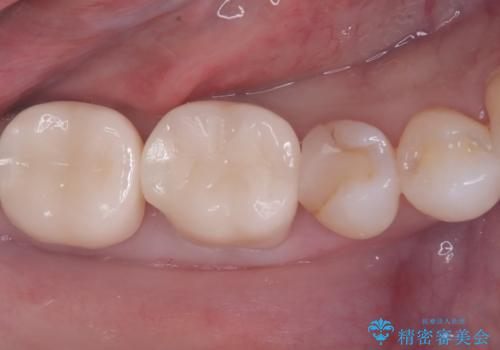

- 前歯の変色を主訴に来院されました。

歯茎のラインを整える手術を行ったあとは、しばらく待ってから被せ物の治療を行っていきます。